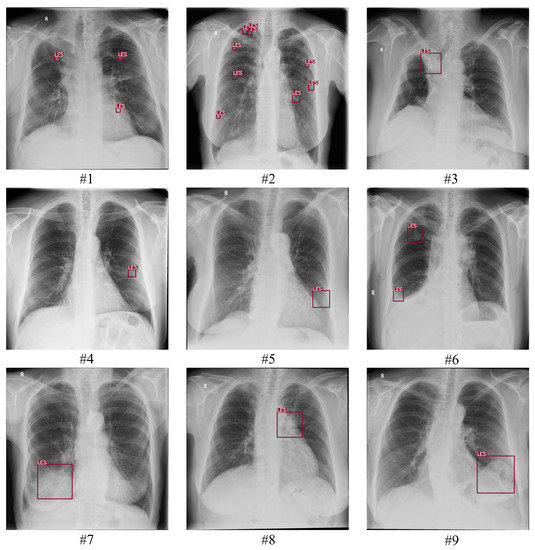

| LES+ Abnormal | A consensus of 2/3 is required to confirm the presence of one or more pulmonary lesions. In addition, CXR may contain other pathological abnormalities. A consensus of 2/3 is required to confirm these. |

| LES− Abnormal | A consensus of 3/3 is required to confirm the absence of any pulmonary lesions. In addition, CXR contained other pathological abnormalities. A consensus of 2/3 is required to confirm these. |

| Normal | A consensus of 3/3 is required to confirm the CXR did not show any pathological abnormalities. |